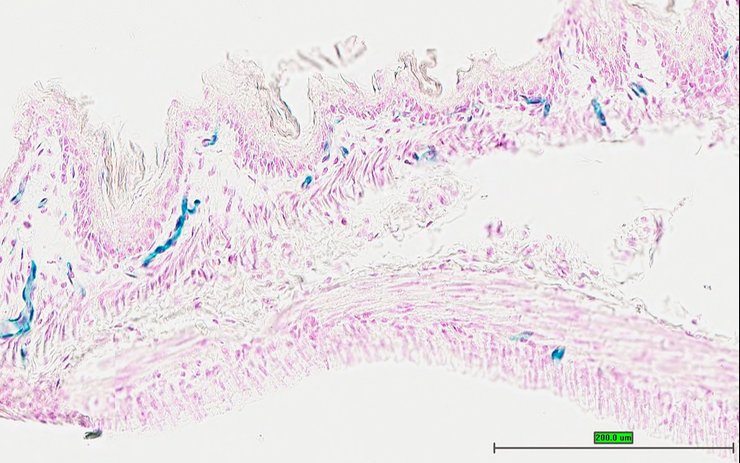

TS28: bladder Present UC Davis_1872999

Specimen UC Davis_1873000: postnatal adult; Ch25htm1.1(KOMP)Vlcg/Ch25h+ (more )

Structure Level Pattern Image Note

TS28: bladder Present UC Davis_1873000

TS28: bladder Present UC Davis_1872947

Specimen UC Davis_1872948: postnatal adult; Ch25htm1.1(KOMP)Vlcg/Ch25h+ (more )

TS28: bladder Present UC Davis_1872948